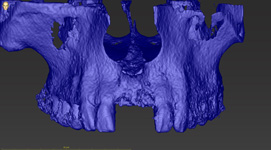

Navigovaná implantologie využívá technologii na principu GPS, kdy zobrazuje pozici, směr a sklon zahlubovacích a rozšiřovacích vrtáčků v čelistní kosti v reálném čase. Opět vlastnímu výkonu předchází přesný plán ohledně pozice, směru, sklonu

a hloubky jednoho nebo více implantátů. Chirurgicko-protetický plán vychází opět z 3D rentgenu čelisti, otisku zubů a dásně (scanu zubů a dásně) a finálního návrhu protetické náhrady. Na základě těchto dat je v plánovacím softwaru coDiagnostiX

vytvořen speciální nosič se senzorem, který poté snímá kamera na vrtačce a přenáší reálná data o poloze vrtáčku na obrazovku při výkonu.

Od roku 2015 testujeme na našem pracovišti jednotlivé systémy navigované implantologie z celého světa, v současné době používáme a podílíme se na vývoji systému DENACAM od f. Mininavident AG. Od roku 2019 probíhá na našem pracovišti studie na porovnání přesnosti mezi chirurgickými šablonami a aktivní navigací DENACAM ve spolupráci s Ludwig Maximilian University of Munich (LMU), DSI HUBER Dental Science & Innovation in Munich a Mininavident AG in Basel, CH